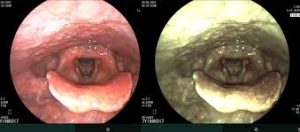

Đây là một kỹ thuật y khoa giúp quan sát trực tiếp bên trong thanh quản bằng ống nội soi chuyên dụng. Phương pháp này cho phép bác sĩ kiểm tra cấu trúc, hoạt động của dây thanh, phát hiện tổn thương, viêm nhiễm hoặc các khối u bất thường trong thanh quản.

Đây là phương pháp nội soi phổ biến nhất, thường kéo dài từ 10-15 phút. Nội soi trực tiếp giúp quan sát chi tiết hơn, hỗ trợ cả chẩn đoán, theo dõi và điều trị bệnh. Nội soi trực tiếp được sử dụng khi cần kiểm tra sâu khu vực thanh quản, dây thanh hoặc lấy mẫu mô sinh thiết.

Một ống nội soi mềm có gắn camera và đèn chiếu sáng được luồn qua mũi hoặc miệng, sau đó đưa xuống thanh quản để quan sát chi tiết khu vực cần kiểm tra.

- Hình ảnh sắc nét, có thể quan sát sâu vào dây thanh và khí quản.

- Quy trình nội soi nhanh chóng, chỉ mất khoảng 10-15 phút.